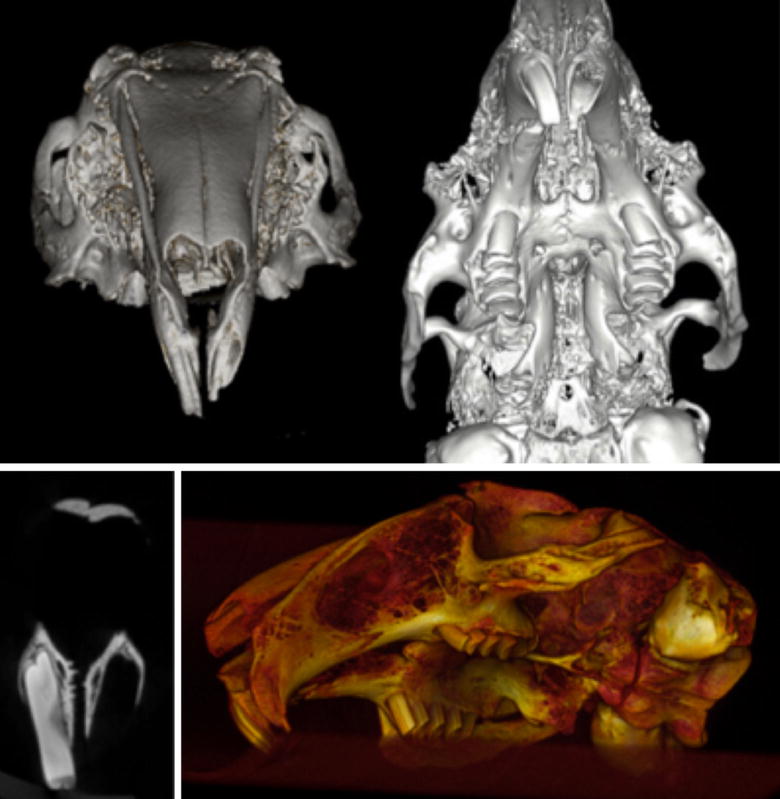

摘要:本研究的目的是在不损害动物的健康情况下建立一种适当模拟临床缺陷环境的组织工程骨替代材料的牙槽突裂动物模型。创裂手术的目的是创造一个完整的齿槽裂,宽的骨缺损,上皮衬里(口腔粘膜)覆盖在裂隙缺损上。方法:对死后新西兰兔的颅骨进行成像调查。一个微型计算机断层扫描影像预试验来证实手术的可行性和缺陷。对16只,8周龄的建立体内齿槽裂手术动物模型进行了测试和评价。结果:临床检查和影像学分析,在所有兔子模拟牙槽突裂手术后8周发现一个广泛的骨骼缺陷延伸到鼻粘膜。结论:我们的外科技术成功地创建一个相当大和可预测的骨移植材料试验模型。该模型允许模拟裂区环境,可用于评价各种骨移植材料在骨形成和愈合潜力方面的效果,而不损害动物的健康。关键词:动物试验 唇腭裂 移植法 组织工程 兔背景:先天性牙槽嵴裂是一种畸形,是由于在妊娠4~12周内未融合原腭引起的。牙槽突裂修复的目的是建立上颌骨牙槽嵴的骨连续性。密封口鼻传播,为口腔修复创造良好的解剖学。应用自体骨、同种异体骨和异种骨移植材料以及各种组织工程骨替代材料进行牙槽突裂植骨。优化现有骨移植材料的质量,寻找新的、更好的骨替代材料是提高临床疗效的关键。各种移植材料的实验测试需要预先建立一个适当的生物学模型来进行实验研究,并评估骨形成和愈合的临床效果。模拟牙槽突裂的动物模型被认为是适当的临床干预试验的实验模型。一些动物模型已被用于检测齿槽裂植骨材料包括小鼠,大鼠,兔,猫,狗,猪,山羊,绵羊和猴。在实验动物中的牙槽突裂的发展是可以实现的,无论是手术或先天所致宫内胚胎发育过程。与大的模型,包括兔子相比,啮齿类动物模型有其固有的局限性。啮齿类动物有较小的长骨,更脆弱的皮层,不在皮质显示骨型重构。兔子没有攻击性,容易观察,在妊娠和成熟方面时间较快。兔的骨组织学与人类骨不太相似。文献报道了兔和人骨密度和断裂韧性的相似性。与灵长类动物和啮齿类动物相比,兔子表现出快速的骨骼代谢和骨转换率,主要是皮质重塑。为了正确地模拟人的体内环境,兔模型是一种适合于牙槽嵴裂实验研究的动物模型。因为兔子是可重复的,精确的,易于内部处理,比较容易麻醉,提供足够大的面积进行测试和可以承受手术创伤大小适当的哺乳动物。方法:微焦点CT(微CT)成像调查:通过对兔颅骨的显微CT成像,获得了骨骼解剖的影像学分析,以评估牙槽突裂的可行性和裂裂手术的计划。使用横断面切片和三维重建进行图像评价。先天性牙槽嵴裂手术与微CT成像:对已死亡的家兔头部进行了外科手术。不需要经过动物伦理委员会的批准,因为这一程序是在一个被处死的动物上进行的,而这只动物曾被用于另一个动物试验项目。根据所提出的程序进行裂裂手术。术后微焦点CT(Micro-CT)评估兔颅骨缺损。体内牙槽突裂形成术:动物、麻醉和饲养 实验手术前30 min 用盐酸甲苯噻嗪5mg/kg,肌肉注射麻醉家兔. 兽医按照已经使用的方法对动物进行镇静、麻醉和护理。研究期间动物单笼饲养,动物按照统一协议饲养观察直到试验结束。新西兰兔体内牙槽突裂手术(n = 16)上颌牙槽突手术部位的准备:兔仰卧位手术在无菌条件下进行。在左侧中切牙外侧进行2厘米左右的线性粘膜切口。沿着牙弯曲,延伸到左中切牙的远中颊角,然后延伸到中线乳头面部左侧中央切口的牙龈边缘。拨开牙龈和软组织暴露上颌牙槽和中切牙牙周附着。随后,皮瓣骨膜下暴露鼻孔。用弯曲的骨膜剥离器保护和提高鼻粘膜不要刺破鼻粘膜。用一个圆形硬质合金牙钻的旋转器械,在左侧中切牙的外侧弯曲处进行侧截骨,以形成一个显露中切牙根的窗口。用小牙挺将中央切牙轻轻脱位向侧壁,后使用兽医拔牙钳提取。进一步的截骨手术去除上下用咬骨钳骨板暴露鼻粘膜不损伤粘膜。然后将骨蜡应用于缺损的骨壁,并近似口腔粘膜。在内侧和外侧用可吸收缝线缝合。伤口中央部分开着,形成一个口袋,可以俯视骨缺损。最后用氧化纤维素填充缺陷。整个手术过程中鼻粘膜保持完整。动物被允许8周的时间来修复缺损和形成上颌牙槽缺损。第二阶段采用相同的手术准备和严格的手术,暴露牙槽骨缺损进行骨移植。牙槽骨缺损部位作一个近缘切口分离口腔。暴露骨缺损,用牙钻固定骨壁。家兔术后直接喂饲软饲料。手术后牙槽突裂的锥形束CT:在造模术后8周,用锥形束CT对兔颅骨进行了术后成像。结果:新西兰白兔颅骨骨调查:新西兰兔上颌前牙的窝藏两配对中切牙和双附件腭侧切牙。中切牙突出,呈半圆形,副腭切牙较小,约占中切牙长度的一半。取出一根中切牙检查颅骨,发现突出的牙齿穿过鼻孔下方的上颌骨,留下一层薄薄的骨,将牙槽窝与鼻粘膜分开。取出的中切牙牙槽窝形成7~8毫米的囊状腔,是牙槽裂研究的理想模型。一旦上下骨板被切除,以产生一个连续的缺陷,模拟常见的先天性齿槽裂患者。先天性牙槽嵴裂手术与微CT成像:兔颅骨牙槽突裂手术的模拟研究显示创建一个适当大小的缺损的可行性。这种缺陷可以很容易地扩展到鼻粘膜来模拟真实的临床缺陷。很容易封闭软组织和缝合黏膜。缺损的三维显示一个宽度为8毫米的三角形牙槽裂缺损。模拟牙槽裂缺损患者的临床表现。新西兰兔体内创造手术牙槽突裂:每只兔的手术时间在15到30分钟之间,所有的程序都可以在没有气管插管的氯胺酮麻醉期间进行。在少数情况下需要额外注射氯胺酮。出血是轻微的,这些动物在手术后立即活跃并表现得很好。动物在手术后的第一天就开始进食了。动物在整个研究期间自由采食。所有兔术后8周存活,直至处死。术后牙槽突裂CT:在8周的愈合后,在一个动物身上进行了计算机断层扫描。缺损部位的三维图显示一个宽度为8毫米的三角形牙槽裂缺损。延伸到与缺陷部位尖鼻并对牙槽窝的深度进行了验证。结论:一种简单、可预测的牙槽突裂兔模型的临床试验。组织工程骨替代材料可以根据现有的解剖结构建立。中切牙的拔牙术,通过将其延长到鼻粘膜来修改拔牙窝,在腭裂修复期的应用简易骨蜡和氧化纤维素材料避免骨的快速生成和缺损的填充。允许8周的愈合产生一个可预测的大小缺陷,可用于以后的移植过程。